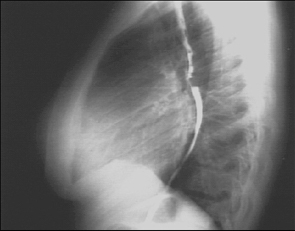

PA and Lateral

Click on the xrays to enlarge them.

Choose the best interpretation of the chest X rays:

Left atrial enlargement and right ventricular enlargement

Left ventricular enlargement and pulmonary congestion

Calcified mitral annulus

Left ventricular enlargement and dilated aorta

Left ventricular enlargement and left atrial enlargement